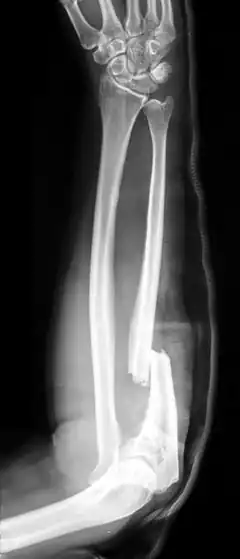

Fracture de Monteggia

La fracture de Monteggia est une fracture osseuse de l'avant-bras sur l'os de l'ulna avec luxation de la tête du radius. Ce traumatisme est dénommé Monteggia en raison de l'étude médicale effectuée par le chirurgien et anatomiste italien Giovanni Battista Monteggia (1762-1815).

Il y a quatre types (selon le déplacement de la tête radiale) :

- I - type d'extension (60 %) - diaphyse ulnaire angulaire antérieure (tendu) et dislocation de la tête radiale antérieure.

- II - Type de flexion (15 %) - diaphyse ulnaire angulaire arrière (fléchit) et de la tête radiale dislocation arrière.

- III - type latéral (20 %) - diaphyse ulnaire angulaire latéralement (courbé vers l'extérieur) et dislocation de la tête radiale sur le côté.

- IV - type combiné (5 %) - diaphyse ulnaire et axe radial sont à la fois fracturés et la tête radiale est disloquée, généralement en avant.